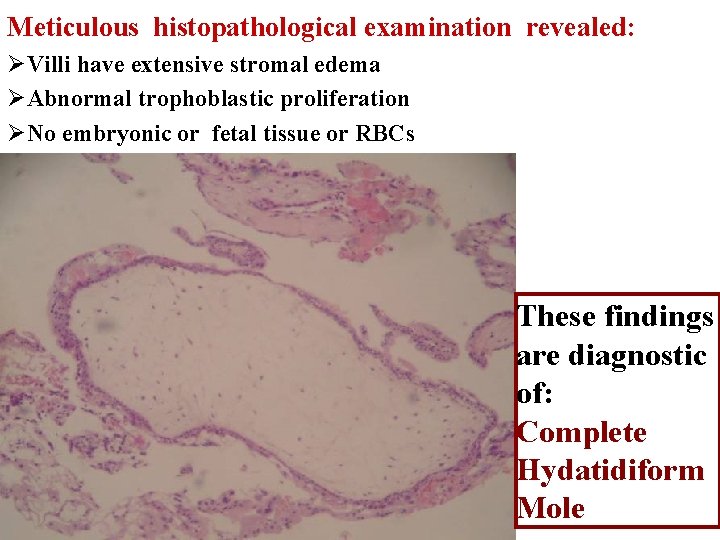

Meticulous histopathological examination revealed: ØVilli have extensive stromal edema ØAbnormal trophoblastic proliferation ØNo embryonic or fetal tissue or RBCs These findings are diagnostic of: Complete Hydatidiform Mole